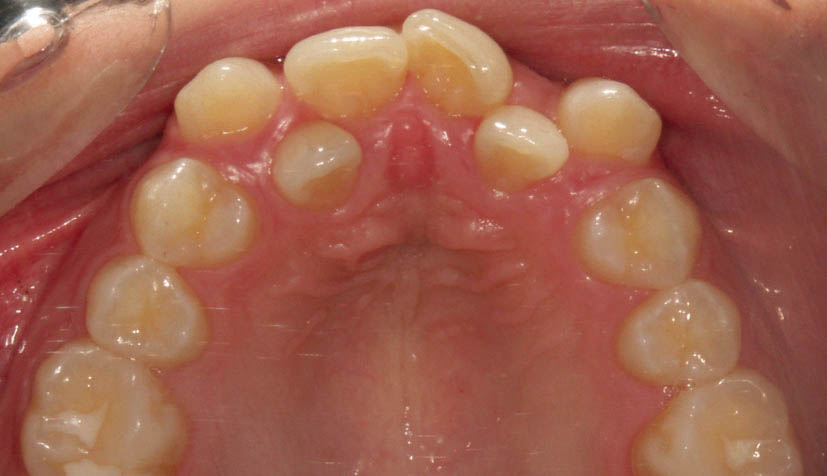

نوع باز آن به نام open coil spring برای باز کردن فضا استفاده میشود. مثلاً دندان لترال در کراس بایت است (شکل 184-1) و فضا برای قرار گیری درون قوس فکی ندارد.

شکل 184-1: وقتی فضا برای درون قوس قرارگرفتن لترال پالاتالی نداریم از فنر open نیتی استفاده میشود تا فضا باز شود.